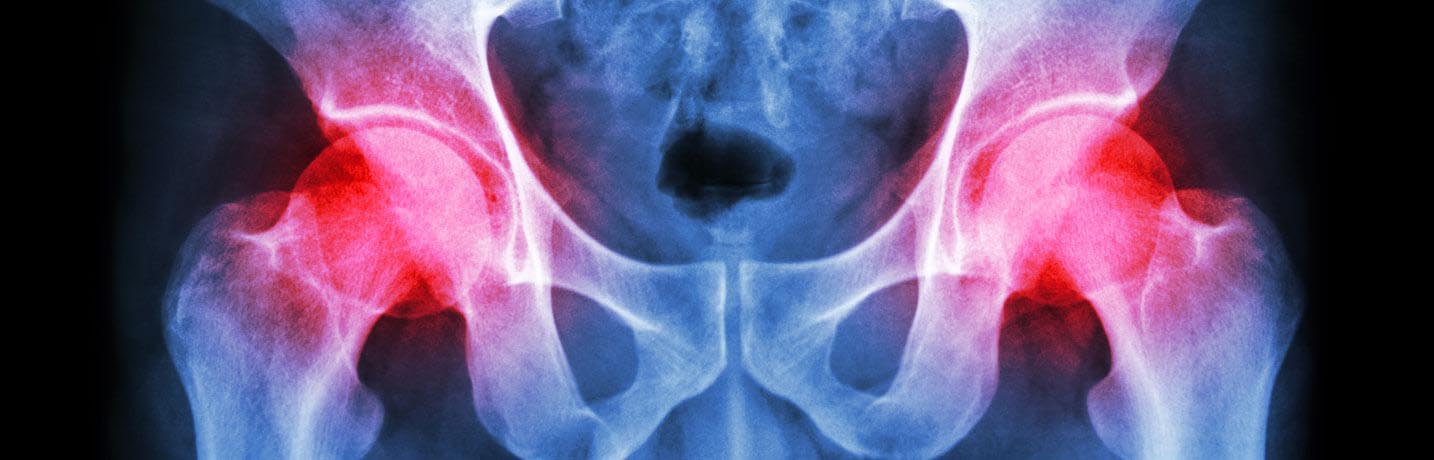

The hip is one of the largest weight-bearing joints in your body. It is shaped like a ball and socket. Total hip replacement is a surgery to replace the ball at the top of the thigh bone (femur) and the hip socket.